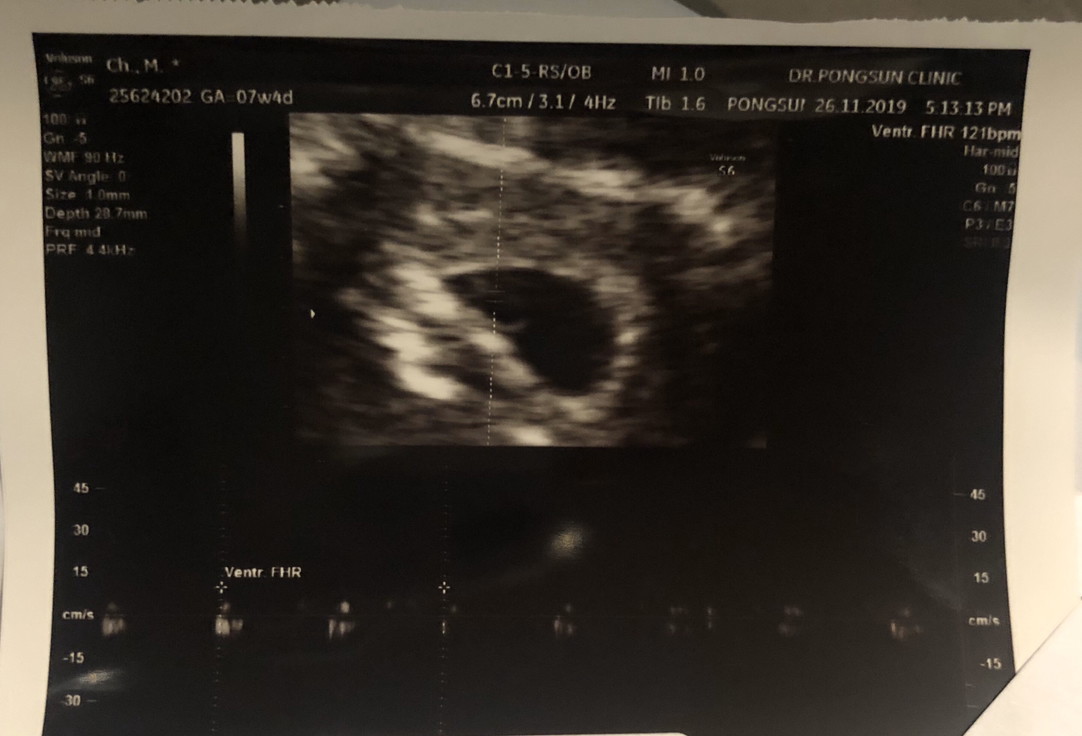

7 สัปดาห์ค้าาา 🥰